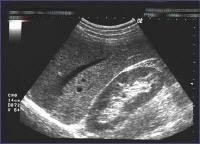

Das Sonographiegerät registriert mit dem Schallkopf die reflektierten Schallwellen und errechnet daraus durch elektronische Umformung ein Bild. Dieses Bild gibt die Größe, die Form und die Struktur der untersuchten Organe und Gefäße wieder. Durch die Abdomen-Sonographie können die Organe des Bauchraums (Leber, Milz, Bauchspeicheldrüse, Gallenblase, Nieren) und Gefäße (z.B. die Bauchschlagader oder die große Hohlvene) dargestellt werden. Krankhafte Vergrößerungen oder Veränderungen innerer Organe lassen sich ebenso darstellen wie Steinbildungen in Galle, Niere oder Harnblase.